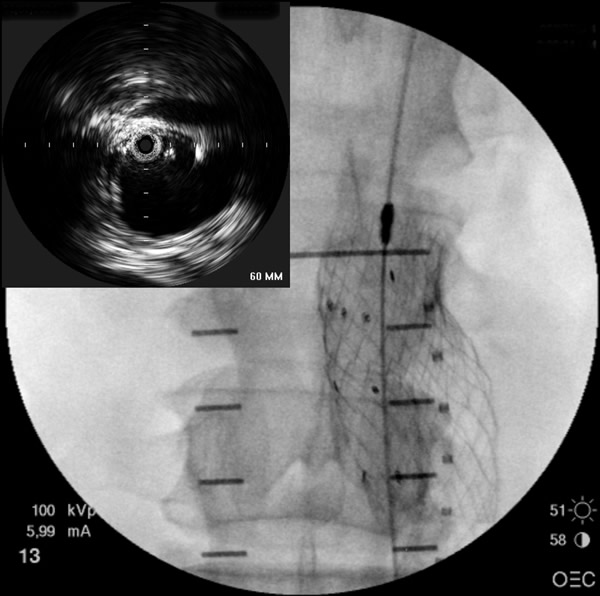

- Initially a 9F introducer sheath is inserted over the primary access guidewire in the more agreeable femoral artery. If there is a concern about aortic rupture, a 12F sheath may be used in order to accommodate large diameter occlusion balloon. A 5F Bern or multipurpose catheter is introduced to facilitate guidewire exchange to a stiff wire (such as the Meier wire or Amplatz). This wire will straighten tortuosity of the access vessel and improve tracking capability of the introduced catheters and devices. An intravascular ultrasound (IVUS) catheter is advanced over the stiff guidewire for inspection of the abdominal aorta. The use of IVUS allows the surgeon to interrogate the entire abdominal aorta and the iliac vessels and to map out (on the fluoroscopic screen) the renal and internal iliac arteries without the use of contrast/fluoroscopy. On the contralateral side, a 5F pigtail catheter to be used for angiography is introduced over the initial guidewire.

- The pigtail catheter is used to perform an aortogram of the abdominal aorta and the iliac arteries. After the angiogram is performed, the proximal neck is evaluated. The length and the diameter of the proximal and distal neck are measured using the preoperative CT scan and the intraoperative IVUS, as well as the angiogram. The details of these imaging modalities will be discussed within the Endoluminal Technology Portal. Based on these measurements, the main trunk’s and iliac arteries’ length and diameter are chosen. On the side of the device’s main trunk and ipsilateral limb introduction an 18-24F sheath (depending on manufacturer’s requirements and size of the stent graft) will eventually be inserted, and on the contralateral side a 12-17F sheath.

- The contralateral limb of the endograft will be introduced over another stiff guidewire inserted from the contralateral femoral artery. Deployment of the contralateral limb of the endograft is most often accomplished through retrograde cannulation of the contralateral limb gate of the main trunk, but other methods can be employed if difficulty is encountered. Cannulation of the contralateral limb gate from a retrograde femoral artery approach is commonly achieved by first using a maneuverable guidewire and steerable catheter. Antegrade or crossover cannulation involves passing a guidewire from the ipsilateral limb to the contralateral limb gate of the endograft, which can be accomplished with a curved catheter (such as SOS-Omni). The wire may be retrieved on the contralateral limb using a snare device. Cannulation can also be achieved using an approach from the brachial/radial artery. To confirm that the guidewire is inside the endograft and not between the graft and vessel wall, a pigtail or other curved catheter can be inserted over the guidewire. The ability to rotate the catheter freely without resistance provides a “relative” assurance that the guidewire is within the endograft (rather than between the endograft and the aortic wall). Also, anteroposterior and oblique fluoroscopic views may help confirm the location of the wire. However, while these “tricks” work well in a majority of cases, they may fool the surgeon in some instances. The only accurate way to confirm the location of the wire within the contralateral gate is to advance the IVUS catheter and visualize the contralateral gate.